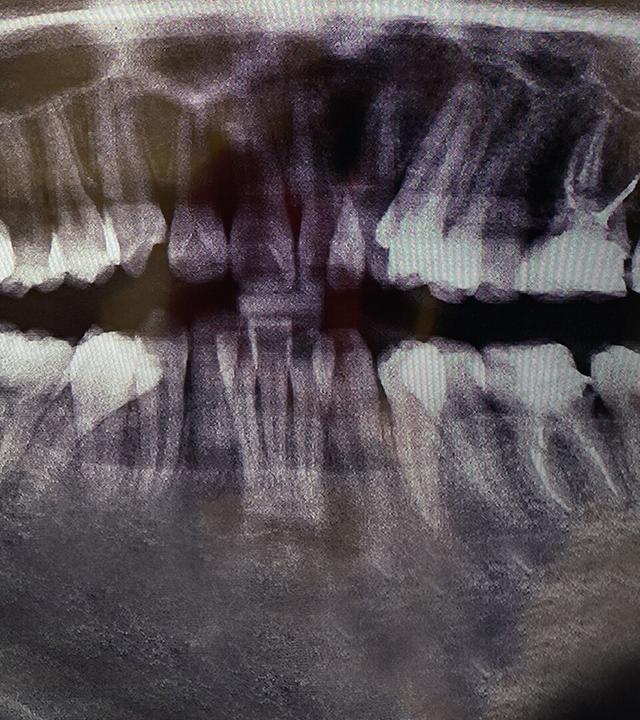

Der Weg zum Hollywood-Lächeln schien nie einfacher. Egal ob bei Facebook, Instagram oder auf Werbe-Plakaten: Überall wird es beworben. Doch schiefe Zähne begradigen, das konnten früher nur Kieferorthopäd*innen. Nun scheint es eine günstigere Alternative zu geben: Unternehmen versuchen mithilfe von riesigen Werbekampagnen, Kundinnen und Kunden für ihre neue Behandlungsmethode zu gewinnen - mit unsichtbaren Zahnschienen zum selber einsetzen. Wir haben uns das Geschäftsmodell und die Preise genauer angesehen und fragen: Dürfen die das?